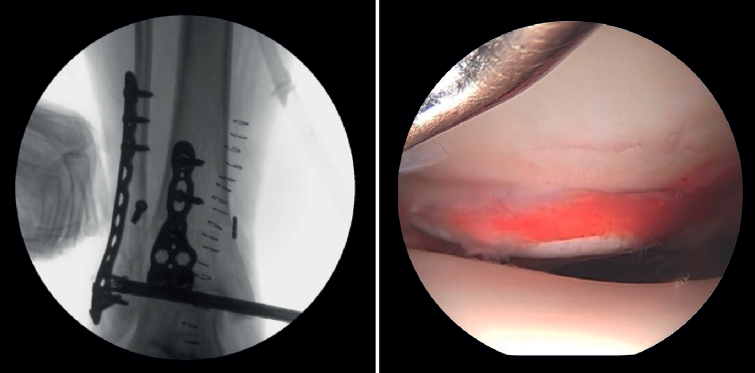

- Assessment of reduction of the posterior malleolus: arthroscopy can be used to verify reduction of the posterior malleolus(5) (Figure 2).

Arthroscopy assists ORIF in evaluating the congruence of the joint surface. It is especially useful for reduction of the medial malleolus. The malreduction rate in medial malleolus fractures is 22.2-32.6%(15,16). Initial arthroscopy allows us to determine whether tibial malleolus reduction can be performed in an open or closed manner. In cases with significant displacement, open synthesis is chosen, always maintaining arthroscopic control during the procedure to ensure precise reduction and avoid rotation of the distal fragment (Figure 4).